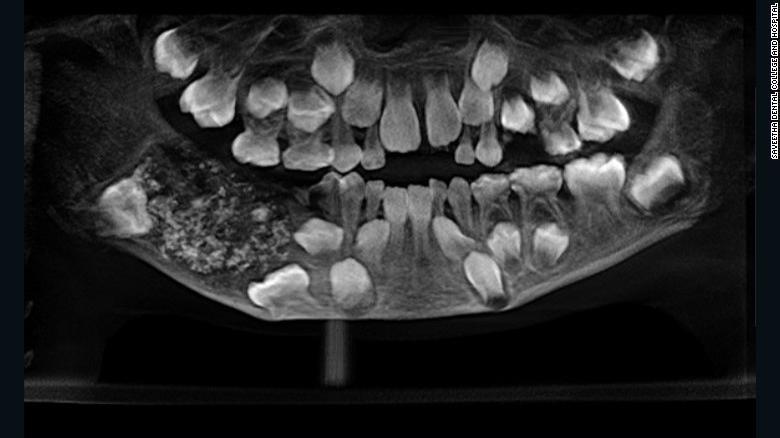

Cậu bé 7 tuổi ở thành phố Chennai than phiền về việc hàm bị đau và sưng trong thời gian dài. Khi đến bệnh viện, các bác sĩ phát hiện cậu có đến 526 chiếc răng.